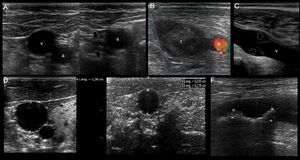

In the short axis, the veins are more oval than round, have an anechoic content, their walls are thin, they are fully compressible and, lastly, they are not pulsatile. On the contrary, the arteries are round, also have an anechoic content, have a thicker wall in comparison with veins, are poorly compressible and, lastly, they have pulsatility2,7 (Fig. 3A).

Ultrasonographic (US) appearance of the vessels. (A) Vessels in short axis, v: vein; a: artery; (B) vein (v) in long axis; (C) artery (a) in long axis; (D) vein flow demonstrating phasicity at spectral Doppler; (E) arterial flow demonstrating pulsatility at spectral Doppler; (F) differences between a superficial vein (sv, above deep fascia and muscle) and a deep vein (dv).

In the long axis, the vessels appear tubular (Fig. 3B and C). Valves can sometimes be observed in the veins, with the corresponding normal opening and closing movements. Arteries lack valves. In some cases, when a proximal tourniquet is applied in the veins, stagnant blood, also called rouleaux, can be observed as internal mobile echoes within the vein, fully cleared when compressed with the transducer.

Using color and spectral Doppler, veins normally have a phasic flow (Fig. 3D) (having augmentation with distal compression), whereas arterial flow is pulsatile (Fig. 3E).

Superficial veins are found above the deep fascia and muscle, and they are not accompanied by arteries. On the contrary, deep veins are located below the deep fascia and are always accompanied by arteries (and nerves) in the neurovascular bundle (Fig. 3F).